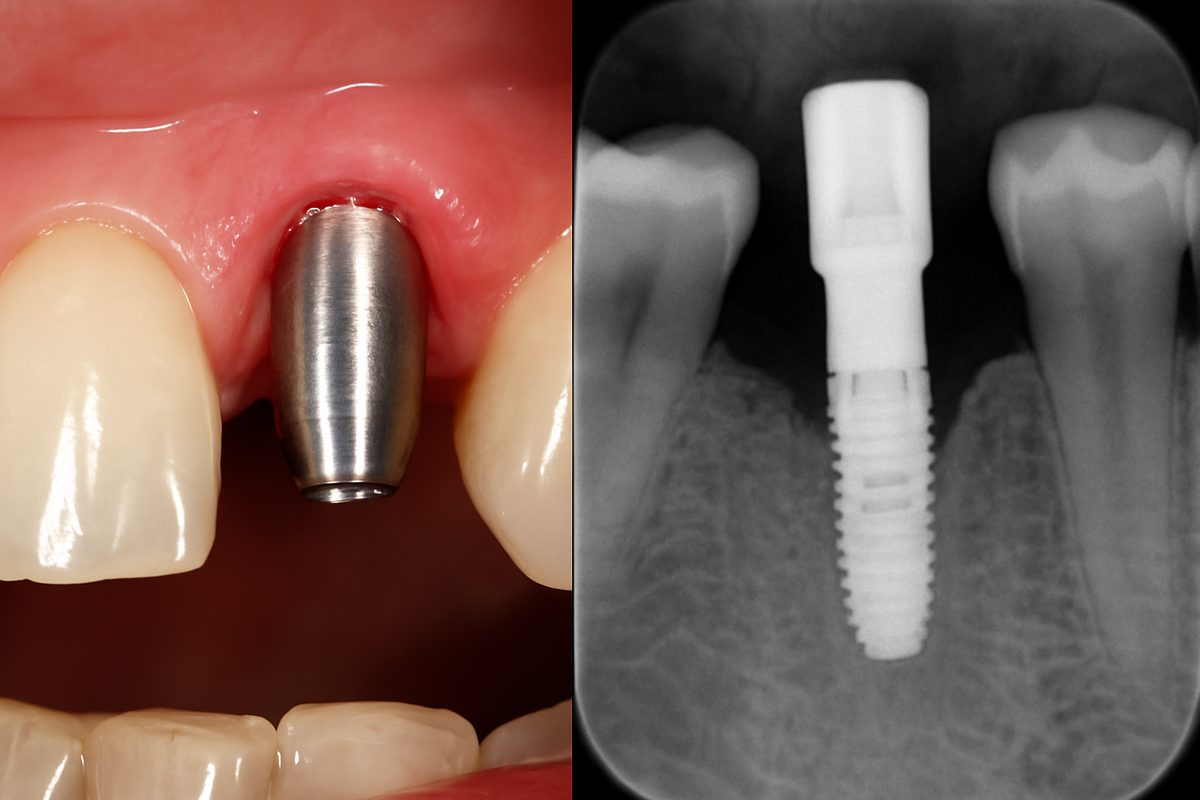

Replacing a front tooth matters more than many people expect. A front teeth implant restores how you look, how you speak, and how you bite.